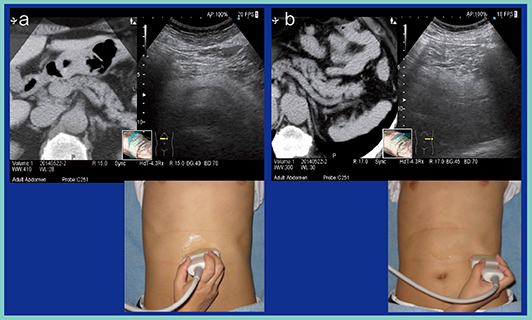

図3は,左の季肋部から左側腹部にかけて,水平にプローブを置いて横走査を行った画像である。後ろの方に脾臓があり,横たわっているのが膵体部から膵尾部であるが(図3 b),ここは正中腹部からの走査では非常に見えづらい(図3 a)。そのため,必ず左側から観察し,脾静脈をメルクマールとする。実は,この走査は肥満体形の被検者の方が観察しやすく,やせ形の被検者では見えづらいため,やせ形の場合は左肋間から観察する。

図3 RVSを活用した膵尾部の観察のポイント